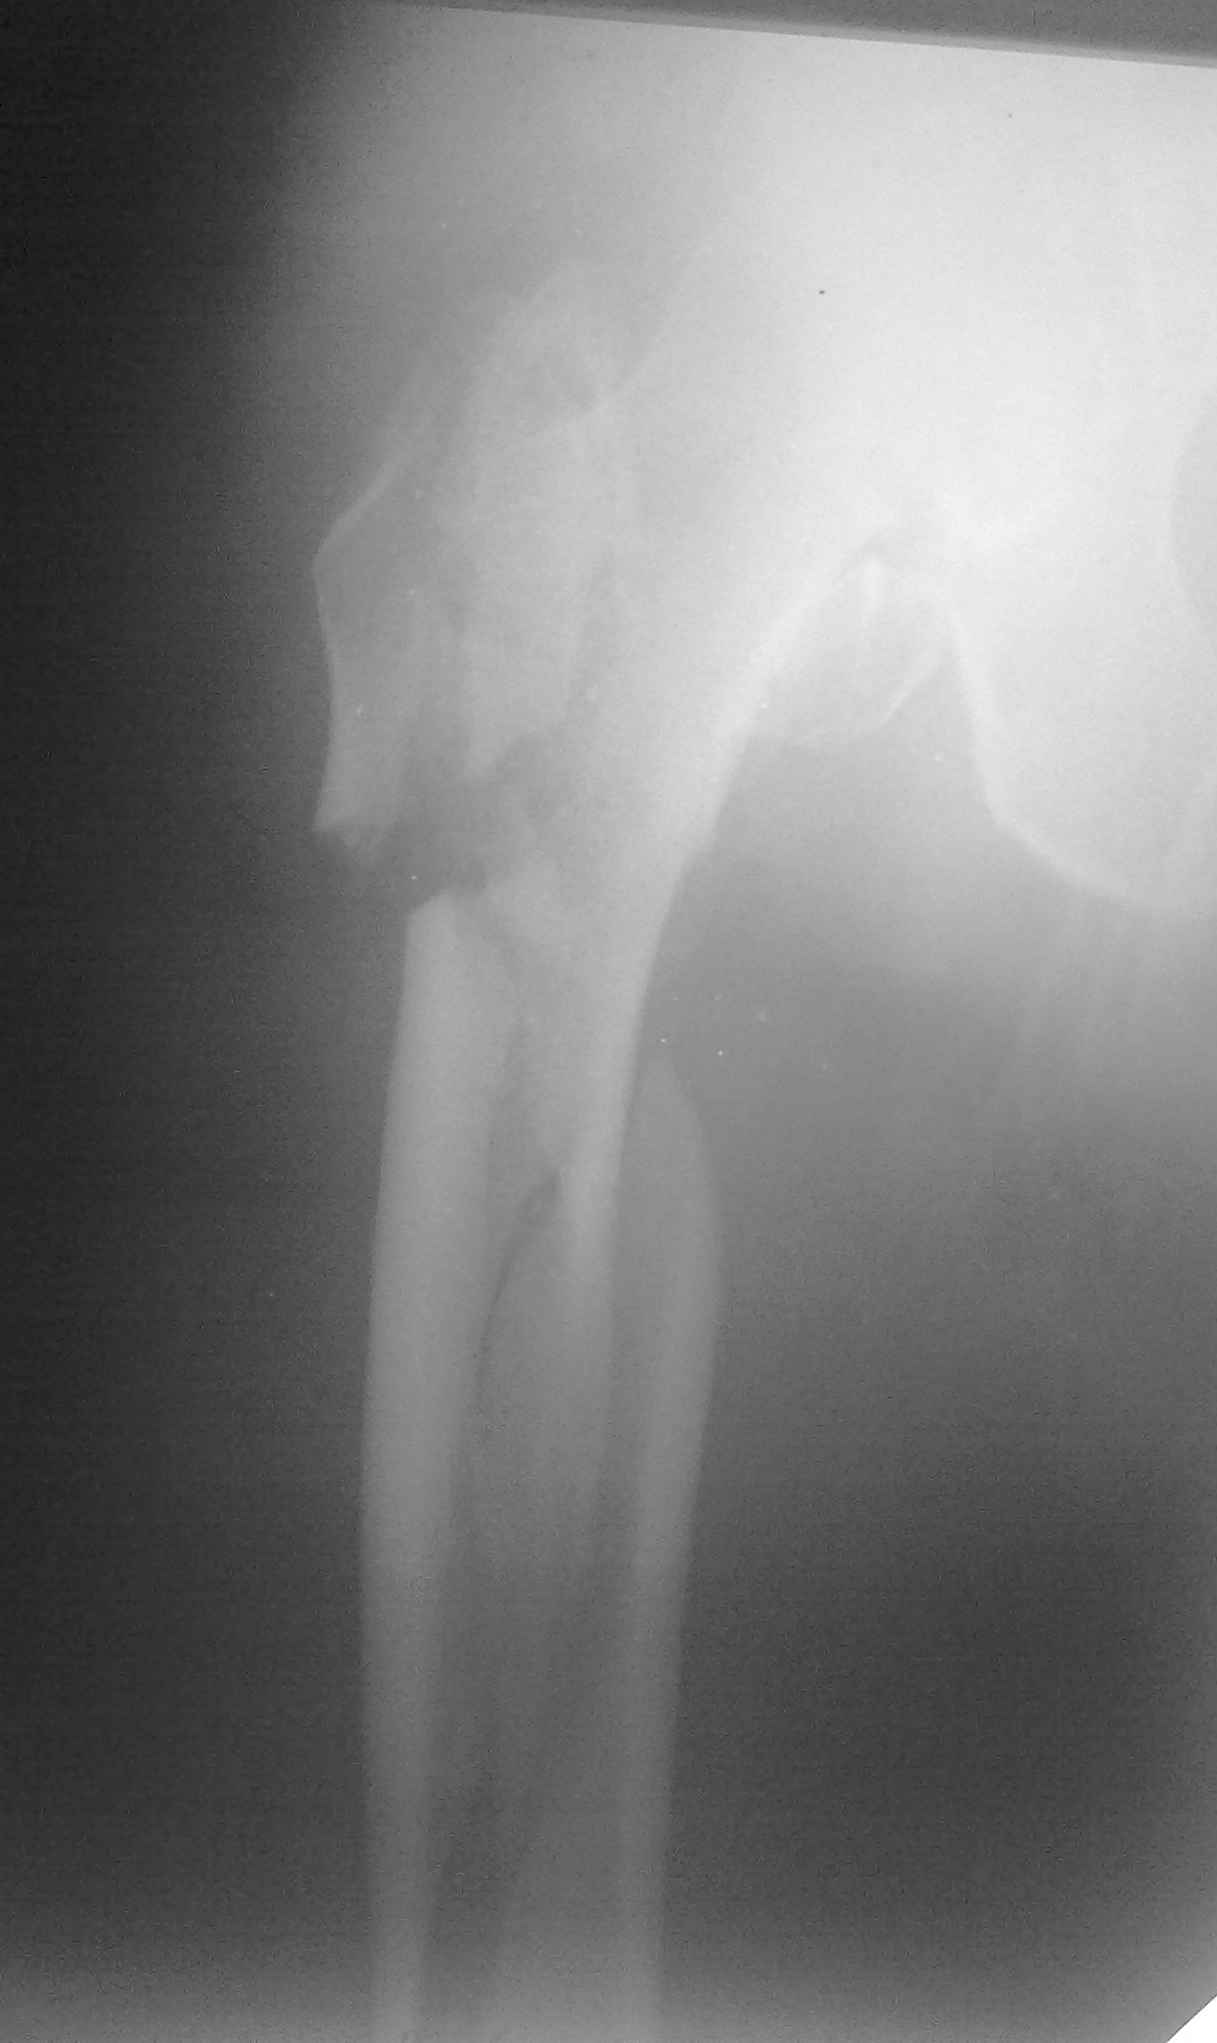

коллеги в наличии есть только проксималный гвоздь chm длинна 260мм.отправить мы ее тоже никуда не можем т.к в облати внедряется тока у нас

Короткая версия 240 мм. Длинные начинаются с 260 мм? Попробуйте имеющуюся железку приложить к рентгенограмме - скорее всего, 260 мм будет маловато. Должна быть возможность связаться с поставщиком и поменять имеющийся гвоздь на аналогичный нужного размера.